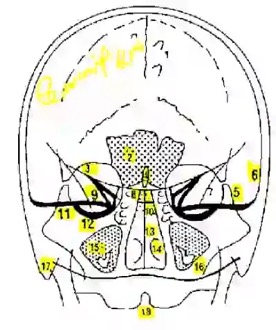

2. INCIDENCE DE TOWNE (WORMS)

Etude fosse postérieure